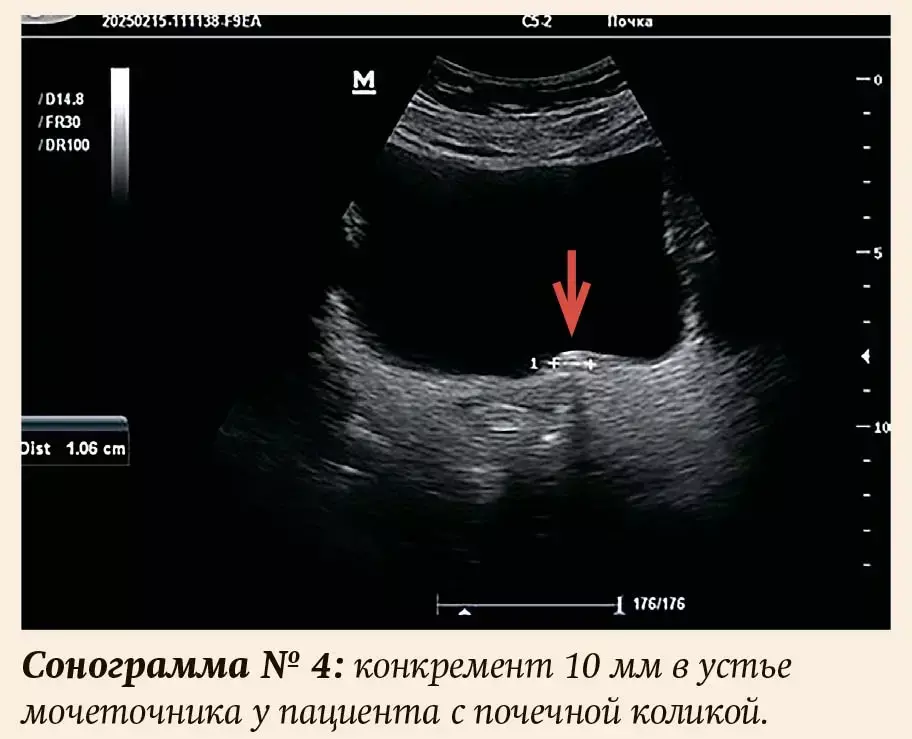

Если камень вызывает внезапное нарушение оттока мочи из почки, течение МКБ приобретает манифестный характер и проявляется развитием характерного симптомокомплекса — почечная колика. Вызвана она острой обструкцией и растяжением мочеточника и почечной лоханки конкрементом, причем чаще относительно небольшого размера, мигрировавшим из чашечки или лоханки. Данное состояние требует экстренной квалифицированной урологической помощи из-за риска грозных осложнений. Встает важный вопрос о своевременной и качественной диагностике уролитиаза.

Диагностические возможности серой шкалы повышаются при расширении собирательной системы. Но и в этом случае не всегда удается визуализировать конкремент, ставший причиной уростаза. Одностороннее расширение мочеточника, почечной лоханки и чашечек является косвенным признаком почечной колики. По данным А. И. Громова, чувствительность и специфичность УЗИ в выявлении данного признака составляют 90,9 % и 93,0 %.

С клиникой почечной колики были срочно направлены для проведения УЗИ почек 17 человек (16 %), 7 — мужского пола (41 %), 10 — женского (59 %); 14 пациентов — лица трудоспособного возраста (82 %). В мочеточнике камень был визуализирован у 4-х (23,5 %).

Размеры выявленных конкрементов — от 3,5 до 25 мм (см. примеры на сонограммах), причем у 5 пациентов (4,7 %) размер не превышал 4 мм. Во всех случаях даже при небольших размерах присутствовали все эхографические признаки конкремента, включая акустическую тень, иногда очень слабую, и/или мерцательный артефакт. Количество разнообразное — от одного до нескольких. Единичный конкремент присутствовал у 55 человек (51 %), у двух (2 %) — коралловидный, остальные имели 2 и более камней. У двух пациентов были выявлены признаки нефрокальциноза. У одной пациентки (57 лет) с несколькими конкрементами в обеих почках и рецидивирующим течением подтверждено наличие аденомы околощитовидной железы. У троих мужчин (2,8 %) с гиперплазией предстательной железы обнаружены камни в мочевом пузыре. Таким образом, проанализировав собственные данные, можно сделать вывод: полученные результаты соответствуют общемировой статистике.